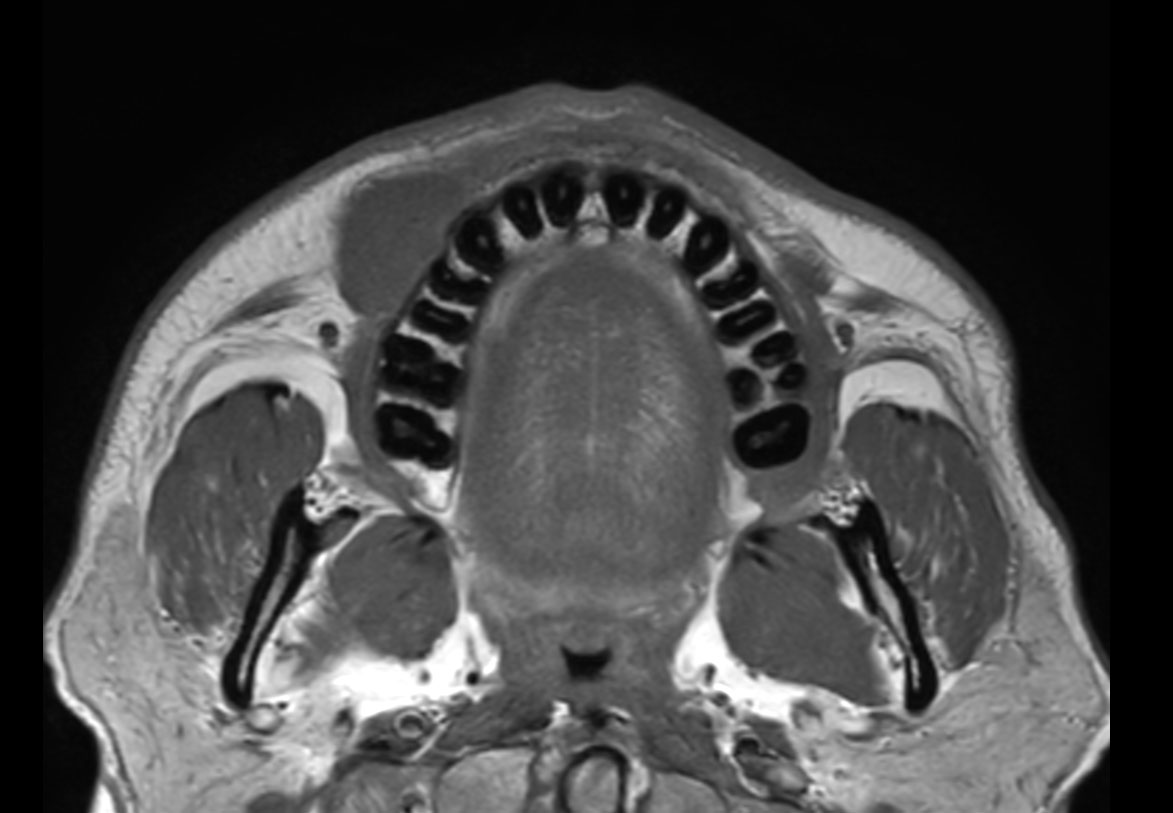

Axial T1w TSE

Axial STIR TSE